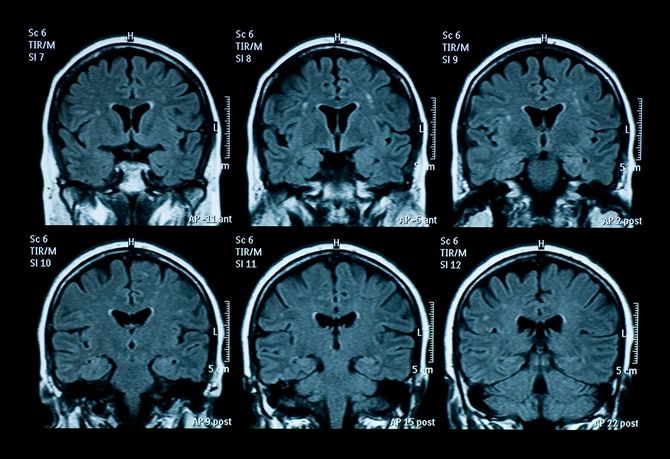

MRIを撮ったところ、脳梗塞によって言語領域が損傷を受けていることがわかり、急遽大学病院へ転院となった。だが、翌日に父親の通夜・葬儀を控えている清水さんは、一人っ子のため、他に頼れるきょうだいはいない。